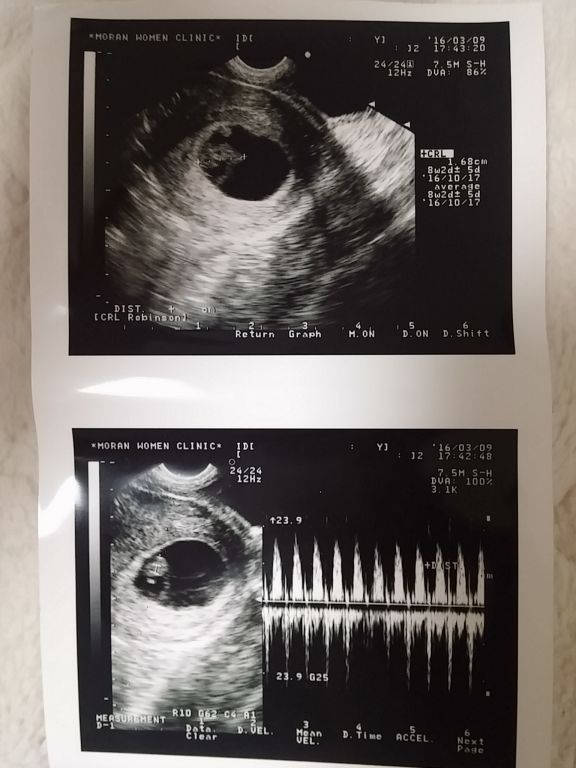

별이 12주~★

2016-04-06

한달만에 별이 보러 병원에 다녀왔습니다. 별이는 별탈 없이 잘크고 있다네요. 입체 초음파로 보니 아빠가 되었다는 사실이 더 와닿습니다. 크기는 5.7cm로 12주 아가에 딱 맞게 크고 있고 심장도 아주 튼튼하게 뛰고 있어요. 초음파 초기에 아주 역동적으로 움직이더니 검사할때 아주 얌전하게 있었어요. 우리 별이 모습을 확인하시려면 아래 동영상 플레이~~^^ BGM은 악동뮤지션의 <작은별> 입니다. 우리Read More →